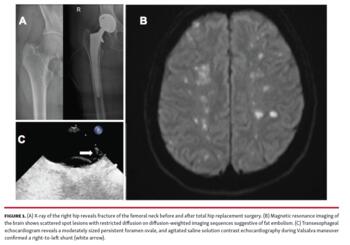

A 62-year-old woman remained unconscious immediately after surgery under general anesthesia for hip fracture (Figure 1A) that resulted from an accidental fall. Medical history included heart failure with moderately reduced left ventricular function. The patient reported no previous neurological symptoms. There were no abnormal intraoperative findings, particularly no decrease of oxygen saturation, no circulatory instability, normal heart rate, and no drop in arterial blood pressure. On physical examination, heart rate was regular at 72 beats/min and blood pressure was 129/82 mm Hg. There were no clinical signs of pulmonary embolism and no further testing was performed. She had no fever, but severely impaired cognition and inappropriate response to auditory and noxious stimuli. Bilateral Babinski signs were positive and tone of upper and lower extremities was unremarkable. Neck stiffness was absent and pupillary light reflex and corneal reflex were preserved. Laboratory findings including glucose concentration and electrolytes were in the normal ranges. An electrocardiogram showed regular sinus rhythm and no abnormalities.

Computed tomography (CT) of the brain without contrast medium revealed small frontal and periventricular white matter lesions and CT angiography was unremarkable. Brain magnetic resonance imaging demonstrated scattered spot lesions with restricted diffusion on diffusion-weighted imaging (DWI) sequences, hyperintensity on T2-weighted imaging, and microhemorrhages on susceptibility-weighted imaging, suggestive of fat embolism (Figure 1B).

Transesophageal echocardiogram revealed a moderately sized persistent foramen ovale (PFO), and agitated saline solution contrast echocardiography and Color-Doppler imaging during Valsalva maneuver confirmed a right-to-left shunt (Figure 1C; arrow).